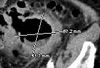

A 26-year-old man presented with sudden onset of palpitations and shortness of breath after incidentally taking tadalafil. He had no other symptoms and no history of illnesses during childhood. He drank socially but denied smoking and use of illicit drugs.